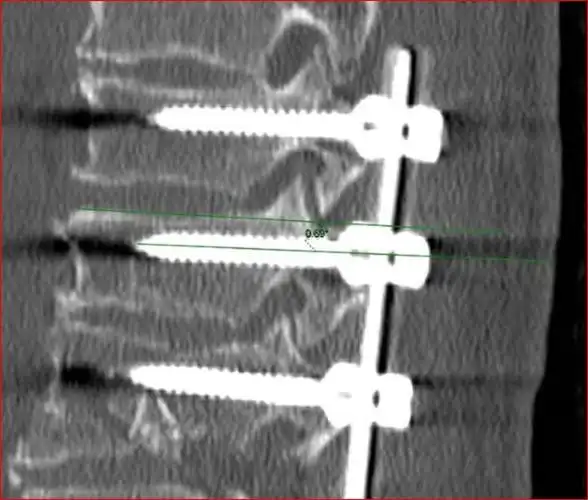

一例椎弓根螺钉尾帽游离病例